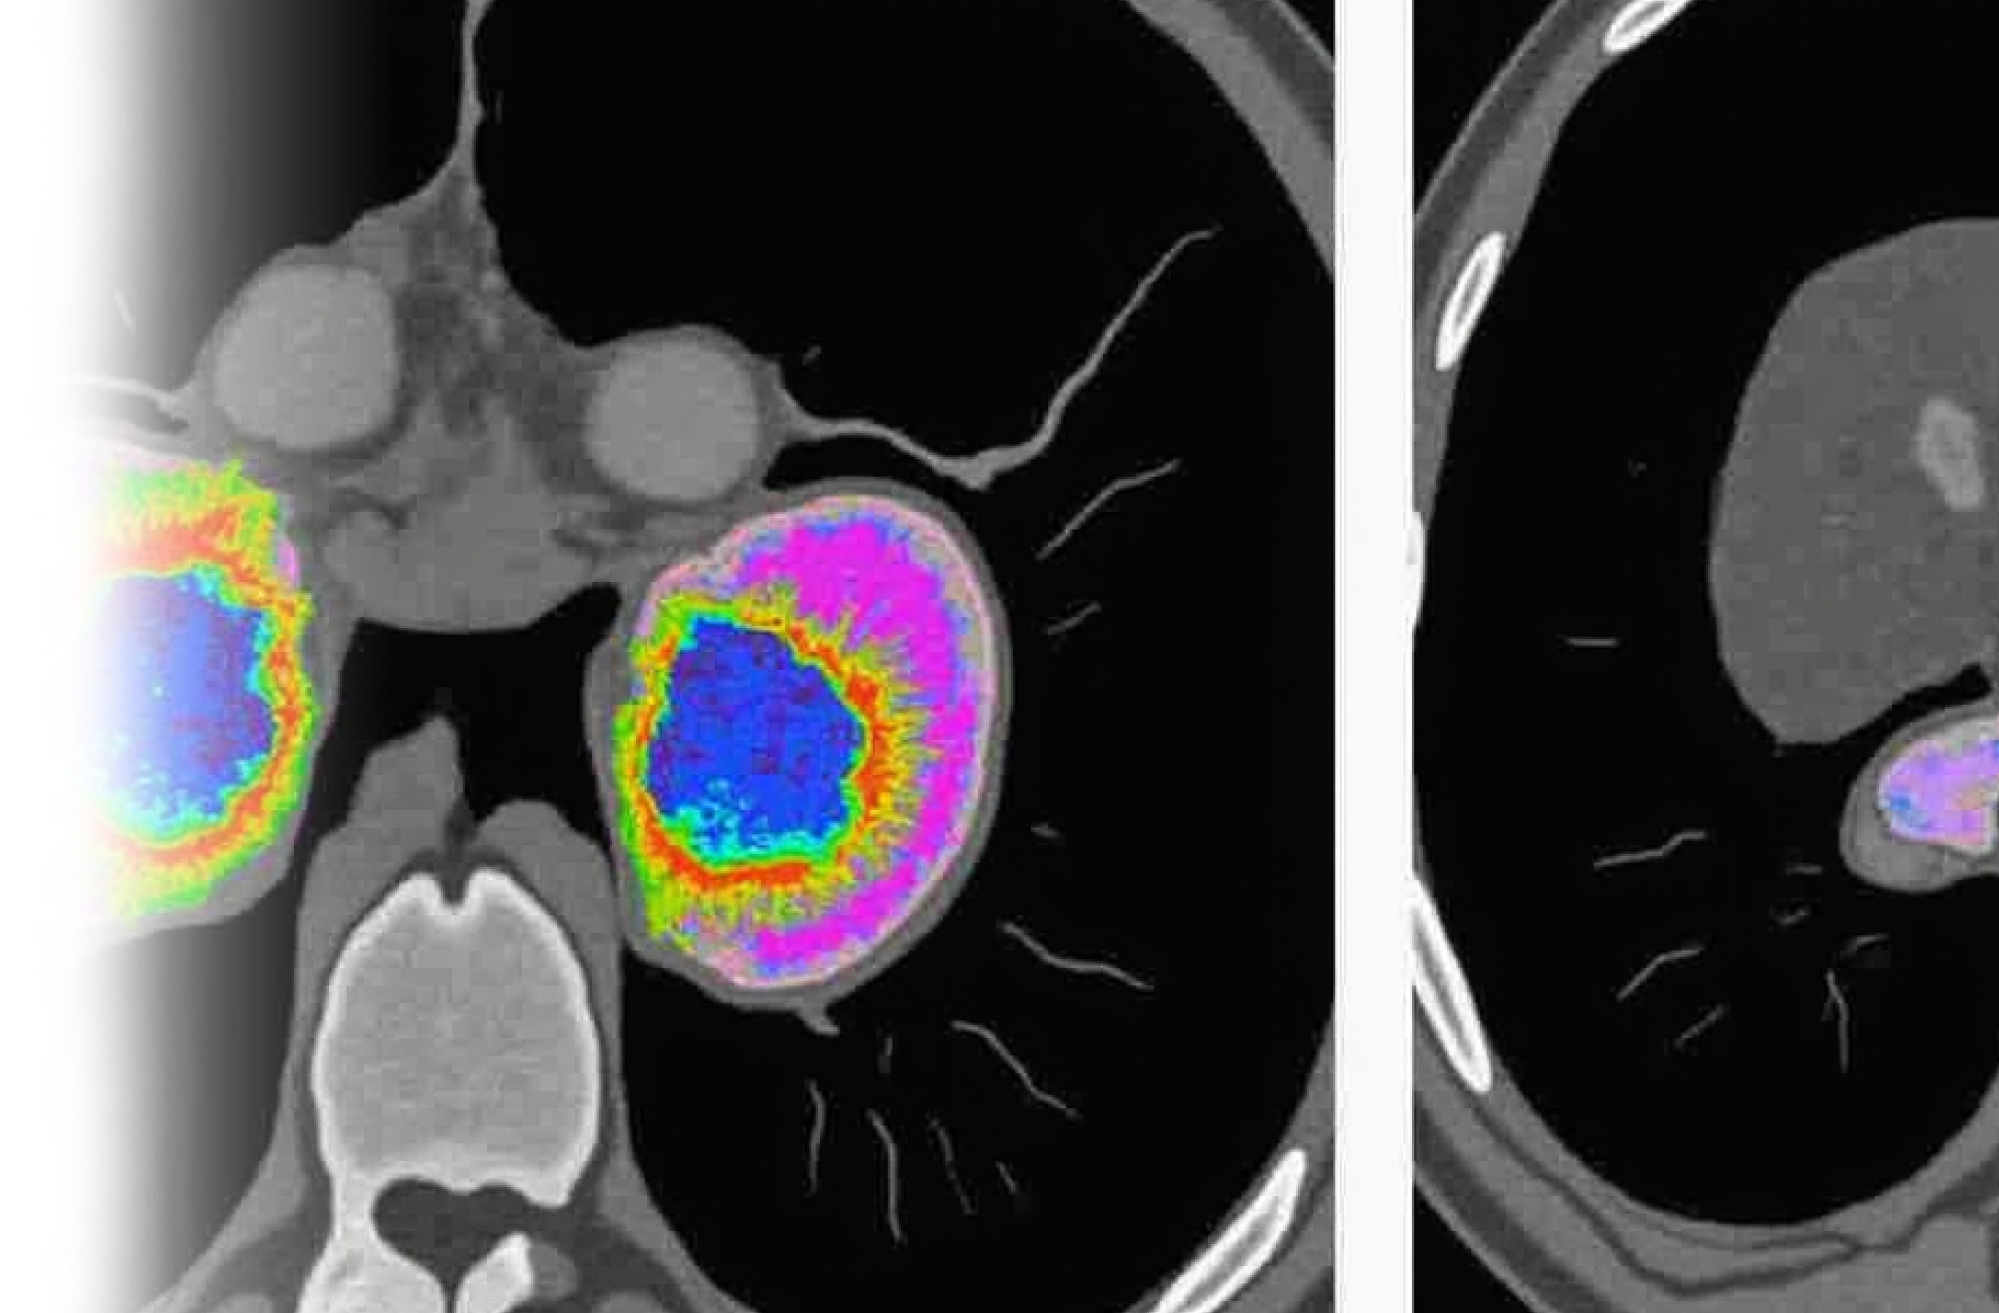

Компьютерная томография почек и надпочечников – важный метод прицельного исследования состояния почек и надпочечников.

Как проводится КТ почек и надпочечников?

После этого пациент ложится на стол сканера, который постепенно перемещается в аппарат. Во время сканирования следует лежать неподвижно, чтобы получаемые трехмерные изображения были четкими и неискаженными.